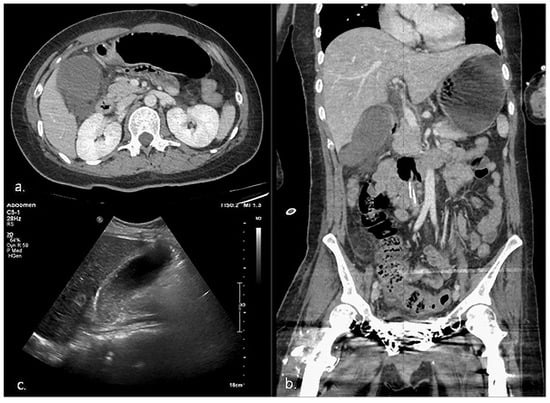

| 2 | HD 105 | 4 | RUQ tenderness * | Fever Elevated CRP * | CT, US | 78 × 49 | 4.1 * | (+) * | (−) | Definite AC |